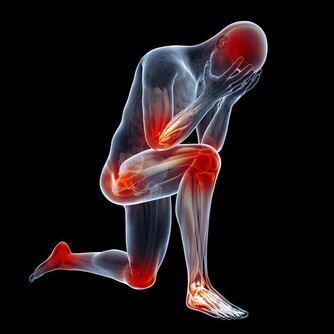

多發性骨髓瘤是一類會抑制人體生產出健康血細胞的癌症。臨床研究表明,多發性骨髓瘤會損傷到患者身體的多個部位,常見的是脊椎、顱骨、骨盆,以及肋骨。在發病初期,患者可能不會出現任何異常症狀。

隨著病情惡化,患者逐漸會感到自己的骨頭在隱隱作痛,骨骼似乎非常脆弱,而且會感到疲倦乏力,刷牙時也會引起牙齦出血,女性患者在經期間的排血量也會異常增多。